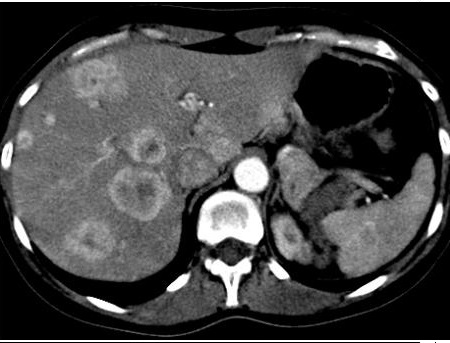

Image TDM des

metastase hepatiques : Sur la TDM a sans

preparation , aspect lesionaire souvent isodense . Les

metastase colorectale souvent hypovasculaire : lesions est

hypodenses au temps portale. Les metastases du rein souvent

hypervasculaire : lesion est hyperdense au temps arteriel

Metastase hypovasculaire du

cancer colique : Aspect lesionaire des metastase est

hypodensse au temps portal |

Metastase hypervasculaire

d'un cancer du rein : Aspect lesionaire hyperdense au temps arteriel

|